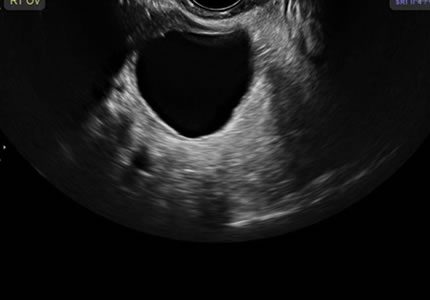

Comprehensive pelvic ultrasound evaluations for a wide range of non-pregnancy female health concerns, symptoms, or referrals.

Symptom-Based & Condition-Specific Scans